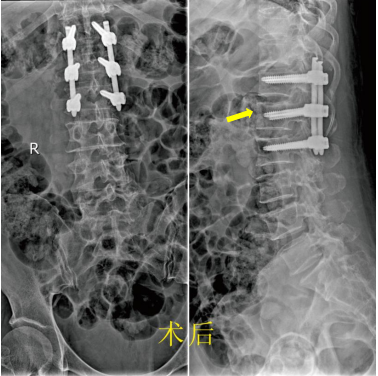

家住九江市经开区的患者王阿姨在家中做事时不慎摔倒,臀部着地,顿时感觉腰背疼痛,腰椎活动受限,并且伴随局部肿胀。随后紧急被救护车送至我院就诊,我院急诊科根据患者腰椎CT检查结果诊断为“腰椎压缩性骨折”,随即收治进我院骨科。 患者入科后,市一医院骨科主任胡斌带领骨科团队进行术前综合评估后,为患者及家属详细讲解病情及手术治疗方式。我院骨科团队为减轻患者治疗痛苦,尽早结束卧床状态,帮助患者尽快恢复正常生活,选择了手术创伤小、恢复快的“经皮植钉骨折复位内固定术”。 在骨科、手术室和麻醉科的充分准备后,在市一医院杨敏捷医师的指导下,整个手术非常顺利。术后第二天复查X线片见压缩性骨折的椎体完全恢复到了接近原来的高度,术后第五天患者就可以配戴胸腰支具下地行走了!